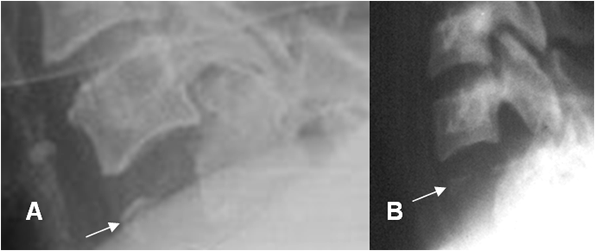

Fig 201 A. Lesión por hiperextensión.

A: TAC reconstrucción lateral. Incremento del espacio intervertebral anterior entre C5 y C6.

Fractura no desplazada en los elementos posteriores. (Flecha gruesa).

B: RM sagital en T2. Ruptura del ligamento intervertebral común anterior. Hiperintensidad del cordón medular, por contusión asociada. (Flecha gruesa).

Fig 201 B. Fractura por hiperextensión.

Rx lateral. Fractura en la parte anterior del cuerpo, con fragmento mas ancho, que alto.